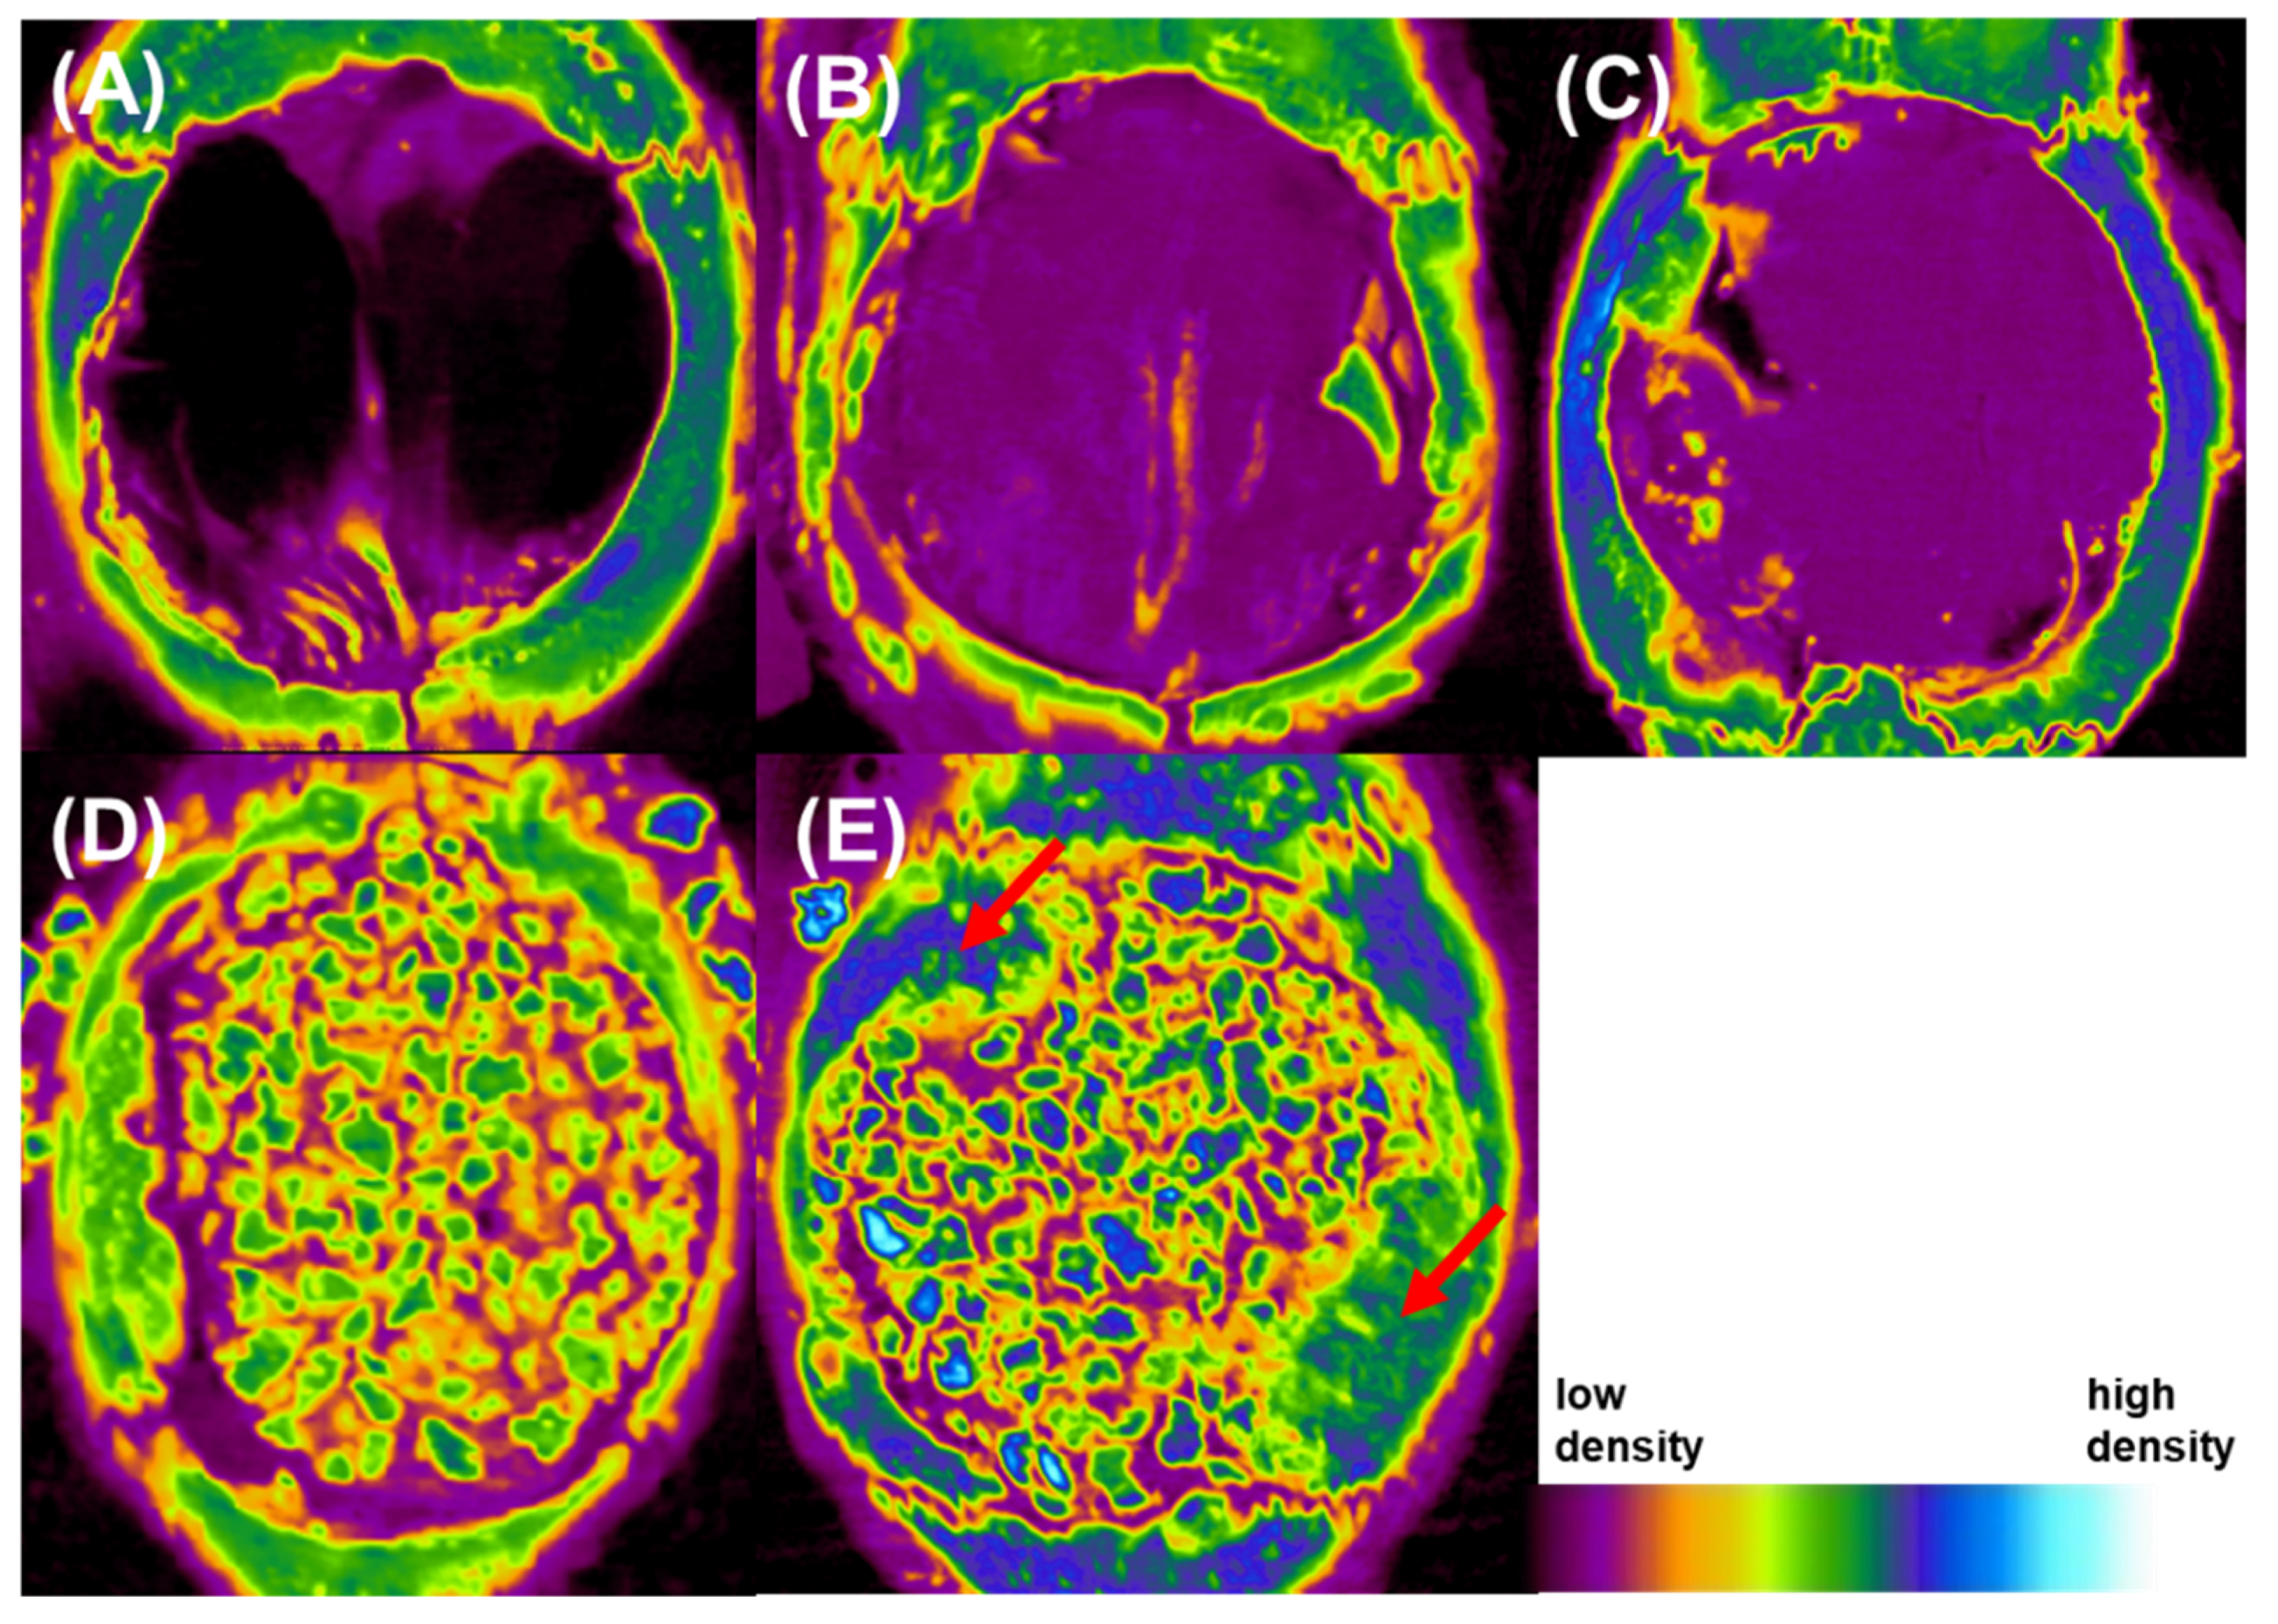

3.8. Bone Morphometric Analysis

3.9. Hematoxylin and Eosin Stain